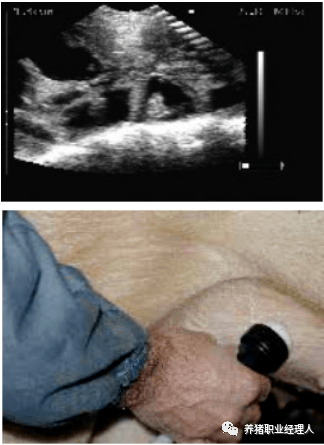

18. B超扫描孕检技术

18.1良好的、有规律的妊娠鉴定是B超扫描

所有的母猪应在第24天或之后扫描。

扫描仪的探头涂上耦合剂后置于腹股沟部。

缓慢地移动探头,直至出现胚胎清晰的图像。

如果图像模糊不清,需要涂更多的耦合剂。

至少要发现3个不同的胚囊,才可判断为妊娠。

如果不确定扫描结果,标记该母猪,并在一个星期内再次扫描。

扫描配种第24天的母猪,大的胚胎囊可以很容易的看到。